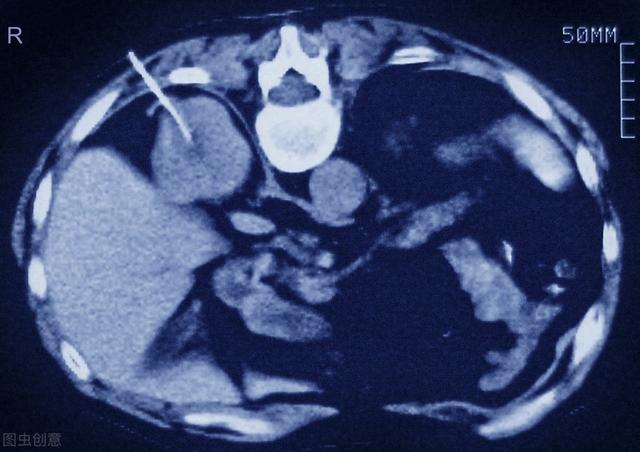

腎生検のCTスキャン

病理診断のための腎生検

血液や尿から得られるバイオマーカーに加えて、腎生検も糖尿病性腎症の退縮を予測する有効な方法である可能性がある。しかし、腎生検は侵襲的な検査であり、臨床現場では非常に不便である。